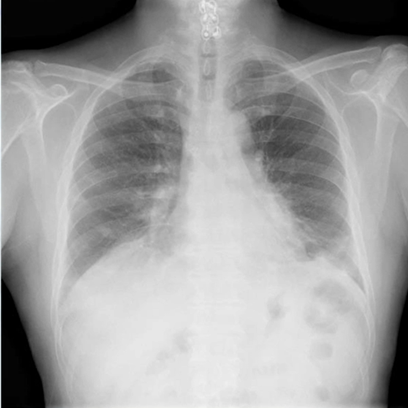

CTだとリバースドハローサインを認める胸部レントゲン写真(X-p):鑑別は結核・悪性腫瘍・膠原病や薬剤になります

所見とすると、両側下肺野に斑状に分布する浸潤影を認め、左心陰影や横隔膜とシルエットサイン陽性です。上記を鑑別に挙げ、精査が必要になります。